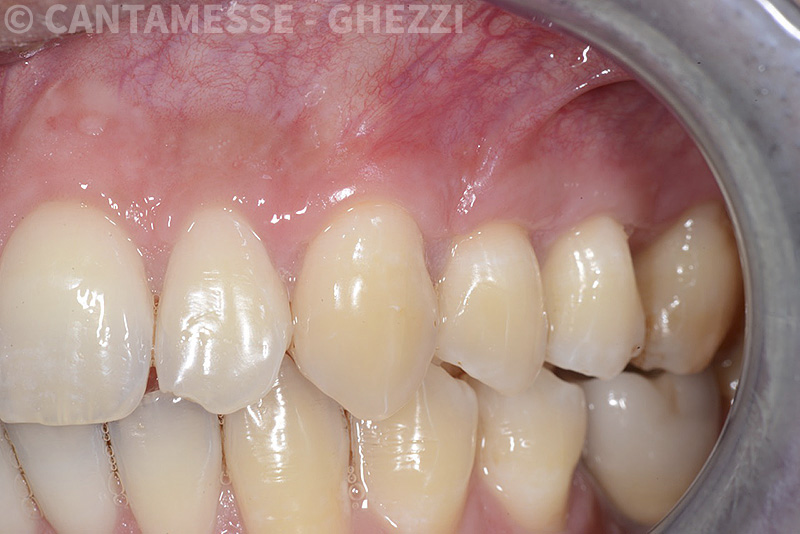

PREMESSA: in seguito all’estrazione dell’incisivo laterale superiore di destra, resasi necessaria per cause batteriche, si decide di affrontare il caso con il posizionamento di un impianto in sostituzione dell’elemento mancante dopo guarigione del sito infetto. Con tecniche rigenerative sia dei tessuti ossei mancanti a causa dell’infezione pregressa, sia dei tessuti gengivali che appaiono inizialmente troppo spostati in alto, si ripristina una corretta morfologia delle parabole (contorni) gengivali e delle papille interdentali (triangoli di gengiva tra due denti vicini).

Vengono utilizzati 2 tipi di provvisori: il primo, cementato ai denti vicini, viene utilizzato dal momento dell’estrazione del dente fino ad impianto osteointegrato (circa 6 mesi); il secondo, avvitato direttamente all’impianto, ha una funzione di prova estetica ma soprattutto di guida per la maturazione dei tessuti gengivali peri-implantari portandoli verso la maturazione completa prima di posizionare la corona finale in disilicato di litio.